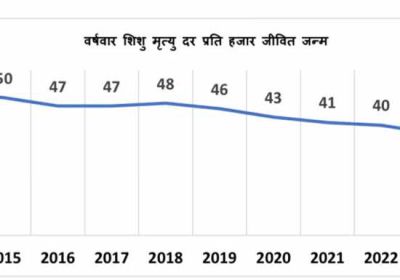

भ्रष्टाचार पर EOW का शिकंजा, नरसिंहपुर में SDM कार्यालय का कर्मचारी रिश्वत लेते दबोचा गया एक दशक में 17 अंकों की ऐतिहासिक कमी के साथ मध्यप्रदेश ने शिशु मृत्यु दर में उल्लेखनीय सुधार दर्ज

एक दशक में 17 अंकों की ऐतिहासिक कमी के साथ मध्यप्रदेश ने शिशु मृत्यु दर में उल्लेखनीय सुधार दर्ज स्कूल फीस को लेकर बड़ा बदलाव, दिल्ली हाईकोर्ट ने प्राइवेट स्कूलों के पक्ष में दिया अहम फैसला